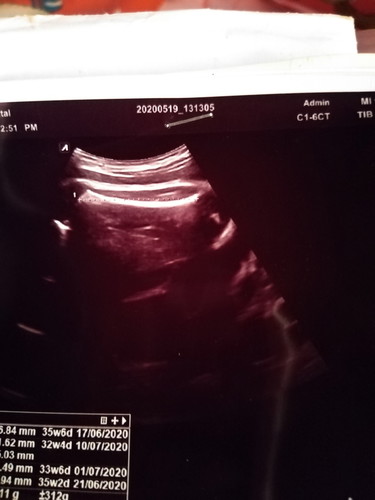

อายุครรภ์36วีค

แม่ๆดูออกไหมคะว่าคืออะไร หมอไม่พูดอะไรเลยค่ะ

มืดไปหมดดูไม่ออกเลยค่ะ 😂

กระดูกต้นขาค่ะ